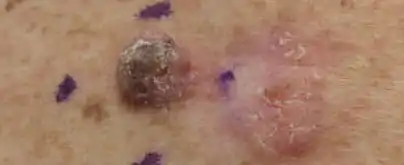

Skin

Squamous Cell Carcinoma, well differentiated, left upper paraspinal back marked for biopsy with adjacent actinic keratosis

Squamous Cell Carcinoma, well differentiated, left upper paraspinal back marked for biopsy with adjacent actinic keratosis Squamous Cell Carcinoma, left lateral canthus marked for biopsy

Squamous Cell Carcinoma, left lateral canthus marked for biopsy Squamous Cell Carcinoma, left ventral forearm

Squamous Cell Carcinoma, left ventral forearm